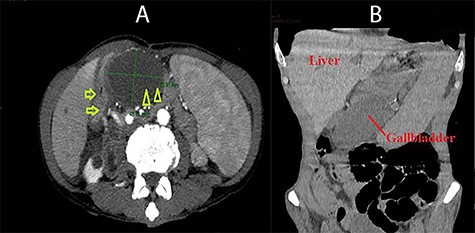

The abdominal computed tomography (CT) showed that the gallbladder was enlarged and distended, with 55 mm in transverse diameter and 7 mm in wall thickness. The gallbladder was seen inside the lesser sac and on the left of the D2 part of the duodenum. It also pushed the stomach anteriorly and superiorly (Fig. 1). The diagnosis of cholecystitis and gallbladder hernia through the foramen of Winslow was made.

Abdominal CT images: A (axial view): duodenum (arrow) and the gallbladder located on the left of the duodenum and posterior to the stomach (arrow head); B (coronal view): the gallbladder was situated under the stomach and far from the gallbladder bed.